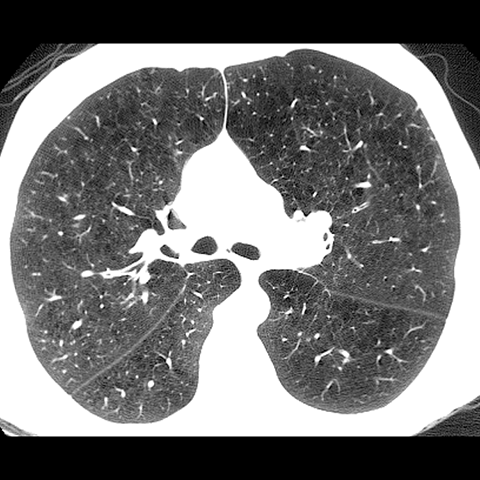

A 62 year-old male presents with chronic shortness of breath (Axial HRCT). [5 of 6]